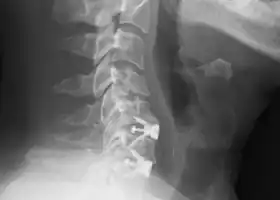

|  X-rays of anterior cervical discectomy and fusion, C5C6 and C6C7. Lateral view. | |

To prevent the vertebrae from collapsing and to increase stability, the open space is often filled with a graft. That can be a bone graft, taken from the pelvis or cadaveric bone; or an artificial implant.[4] The slow process of the bone graft joining the vertebrae together is called "fusion". Sometimes a titanium plate is screwed on the vertebrae or screws are used between the vertebrae to increase stability during fusion, especially when there is more than one disc involved.